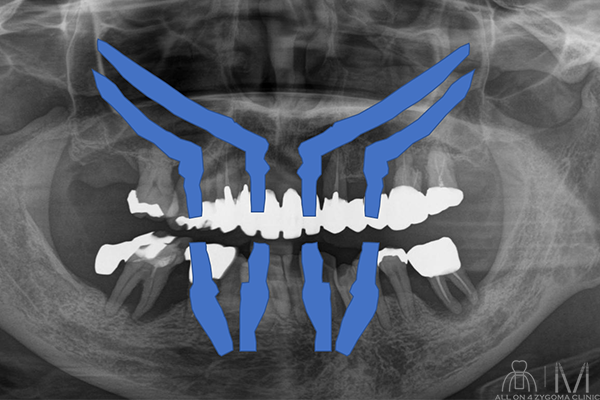

両側上顎は前臼歯歯槽骨に十分なボリュームがないが、頬側に十分なスペースの確保が見込めた。下顎は菲薄な部位はあるものの5┬5を骨整形する事で十分な骨幅の確保が見込めると判断し、この部位に4本ノーマルインプラント埋入予定とした。前歯~小臼歯部で歯槽堤の高低差が大きいことから、安定度を高めるプラットフォームの設計が必要であると考えた。また、頬骨に十分な厚みがある事からザイゴマインプラント4本を用いる上下顎All-on-4治療 を計画した。手術を円滑なものとする為、術中は静脈内鎮静法下での手術を予定した。